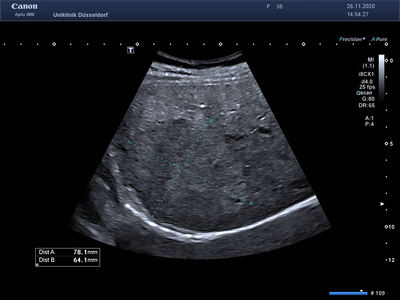

Die Kon­trast­mittelsonographie (KM-Sonographie oder CEUS – contrast enhanced ultrasound) ist ein wichtiges diagnostisches Verfahren, mit dem Tumore der Leber und anderer innerer Organe (z. B. Nieren, Milz, Bauchspeicheldrüse) beurteilt werden können. Neben Tumoren können auch andere Veränderungen dieser Organe charakterisiert werden (z. B. entzündliche Prozesse, Durchblutungsstörungen). Bei erfahrenen Untersuchern hat die KM-Sonographie eine ähnlich hohe Aussagekraft wie eine Computertomographie (CT) oder Magnetresonanztomographie (MRT). Zur Beurteilung von Leberzelltumoren ergänzen sich alle genannten Verfahren (KM-Sonographie, CT und MRT).

Für die KM-Sonographie wird ein Kontrastmittel eingesetzt, welches aus sehr kleinen, von einer Fetthülle umschlossenen, Gasbläschen besteht. Es kommen sehr geringe Mengen (wenige Milliliter) des Kontrastmittels zum Einsatz. Nach der intravenösen Verabreichung verlassen die Gasbläschen den Körper innerhalb weniger Minuten über die Lunge. Die Niere wird dabei nicht belastet, so dass die Untersuchung auch bei Patienten mit fortgeschrittener Nierenerkrankung angewandt werden kann. Unerwünschte Wirkungen (z.B. allergische Reaktionen) treten sehr selten auf und sind unabhängig von bekannten Allergien gegen CT- oder MRT-Kontrastmittel.

Die KM-Sonographie ist nicht nur für die Diagnostik von gutartigen (z.B. Hämangiom, fokale noduläre Hyperplasie - FNH, Adenom) und bösartigen Lebertumoren („Leberkrebs“ oder hepatozelluläres Karzinom - HCC, Gallengangkarzinom oder cholangiozelluläres Karzinom - CCC, Metastasen von Tumoren außerhalb der Leber) und entzündlichen Prozessen (z. B. Abszesse), sondern auch für die Verlaufsbeurteilung dieser Veränderungen hervorragend geeignet.